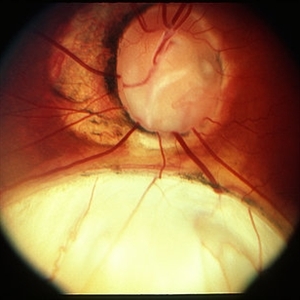

Coloboma

Coloboma

Mar 29 2013 by Henry J. Kaplan, MD

Optic disc and inferonasal choroidal coloboma in the same patient #2.

Condition/keywords: coloboma, coloboma of choroid, coloboma of optic disc